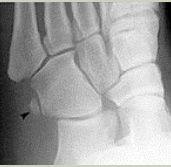

What is this? | Calcaneonavicular coalition (AKA calcaneonavicular bar or anteater's nose) |